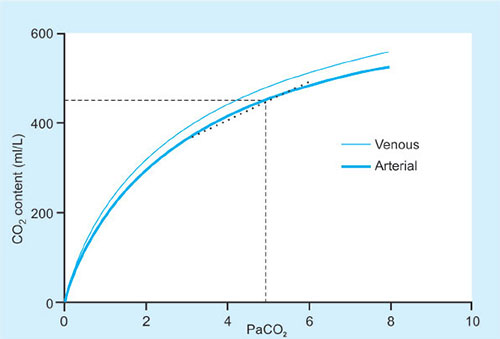

CO2 Dissociation Curve (Fig. 37)

The value for the A-a gradient gives the clinician some idea about the amount of VQ mismatch and shunt that is present in the lungs. A typical normal value would be around 0.5-1 kPa (5 mm Hg) though values up to around 15 mm Hg may be accepted.